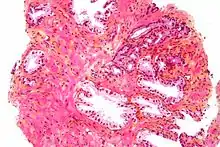

The prostate consists of glandular and connective tissue.[3] Tall column-shaped cells form the lining (the epithelium) of the glands.[3] These form one layer or may be pseudostratified.[5] The epithelium is highly variable and areas of low cuboidal or flat cells can also be present, with transitional epithelium in the outer regions of the longer ducts.[11] The glands are formed as many follicles, which drain into canals and subsequently 12–20 main ducts, These in turn drain into the urethra as it passes through the prostate.[5] There are also a small amount of flat cells, which sit next to the basement membranes of glands, and act as stem cells.[3]

The connective tissue of the prostate is made up of fibrous tissue and smooth muscle.[3] The fibrous tissue separates the gland into lobules.[3] It also sits between the glands and is composed of randomly orientated smooth-muscle bundles that are continuous with the bladder.[12]

Over time, thickened secretions called corpora amylacea accumulate in the gland.[3]

Microscopic glands of the prostate